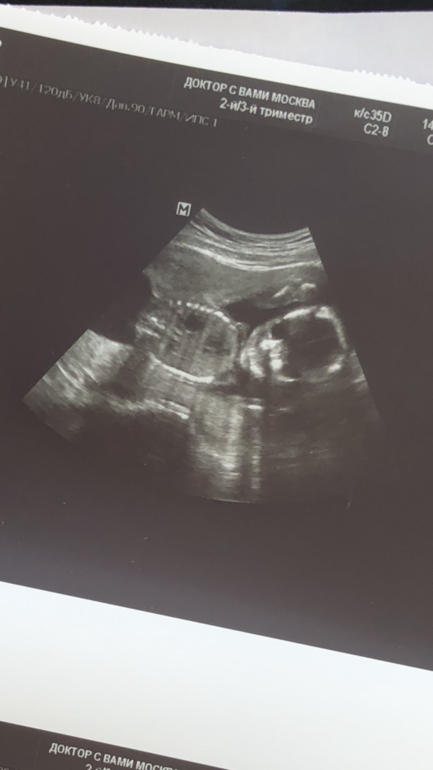

Мальчик или девочка?)

Знаю, что тут девочки глазастые, а я даже не понимаю, что где на фото, кроме головы))

Видно там половые принадлежности или он боком?) 20 недель

На второй Фотке, я так понимаю, должно быть видно. Но, честно, я не понимаю в этих куконях ничего😂

Вроде лежит на боку и лицом к аудитории ) и я вижу, что это девочушка ))

Попку видно). А вам не сказали ,срок большой уже?